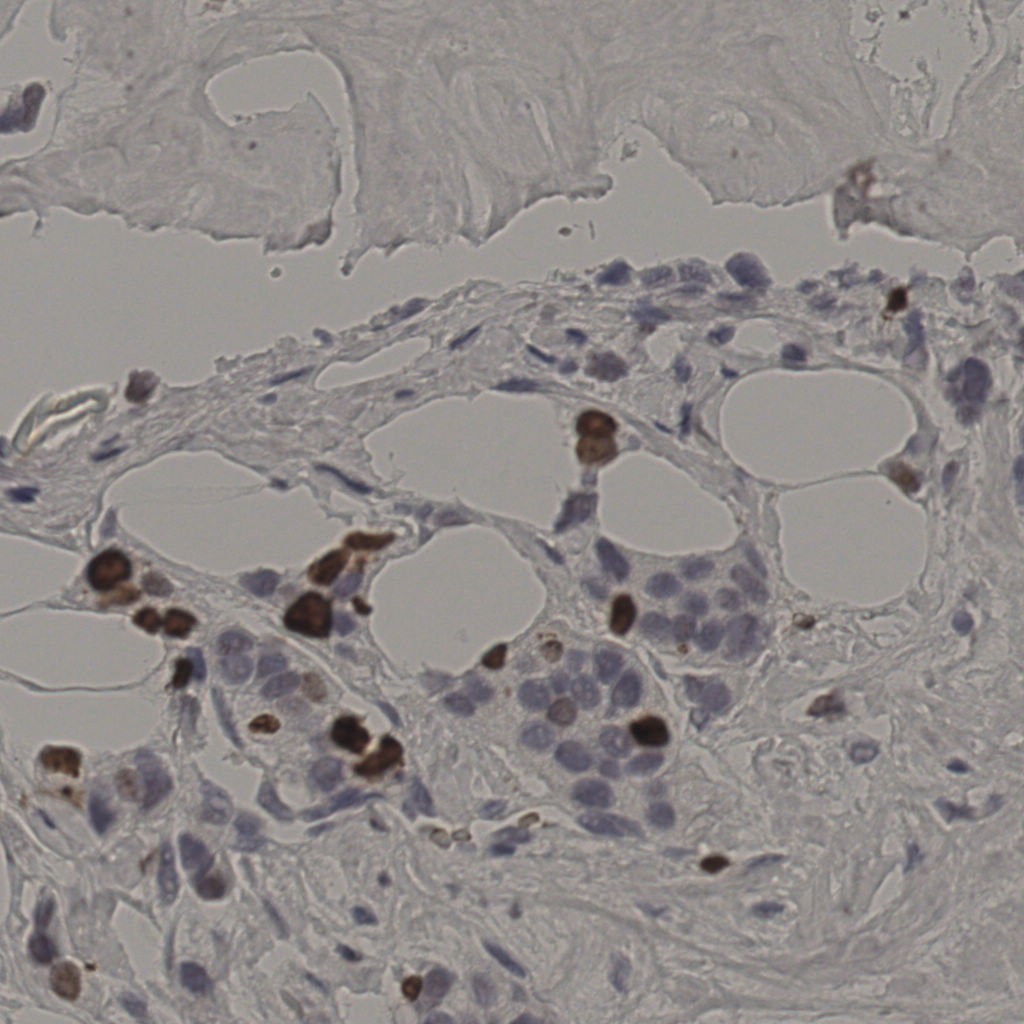

17.75%

Ki67 指数

阴 7986

阳 1723

切片统计

总切片

2640

有效

412

已标记

412

有效率

16%